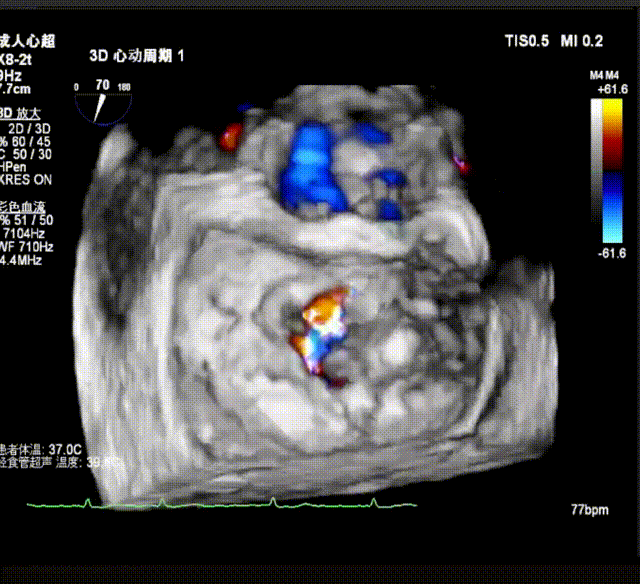

3D enface view示二尖瓣P2P3区瓣叶脱垂,偏心性返流

3D指示下调整瓣膜夹朝向病变区域P2偏P3区

确定瓣膜夹与病变区域垂直后,放下夹片,超声确认前叶后叶都夹合充分,3D检查瓣膜夹位置.

最终释放用多普勒超声评估返流程度,返流情况改善明显,仅存在极微小返流;无瓣口狭窄;肺静脉逆流情况消失,血流动力学显著改善;3D超声下,瓣膜组织桥稳定。术后即刻评估,术后反流消失(MR 0+),术后跨瓣压差2mmHg,手术成功。